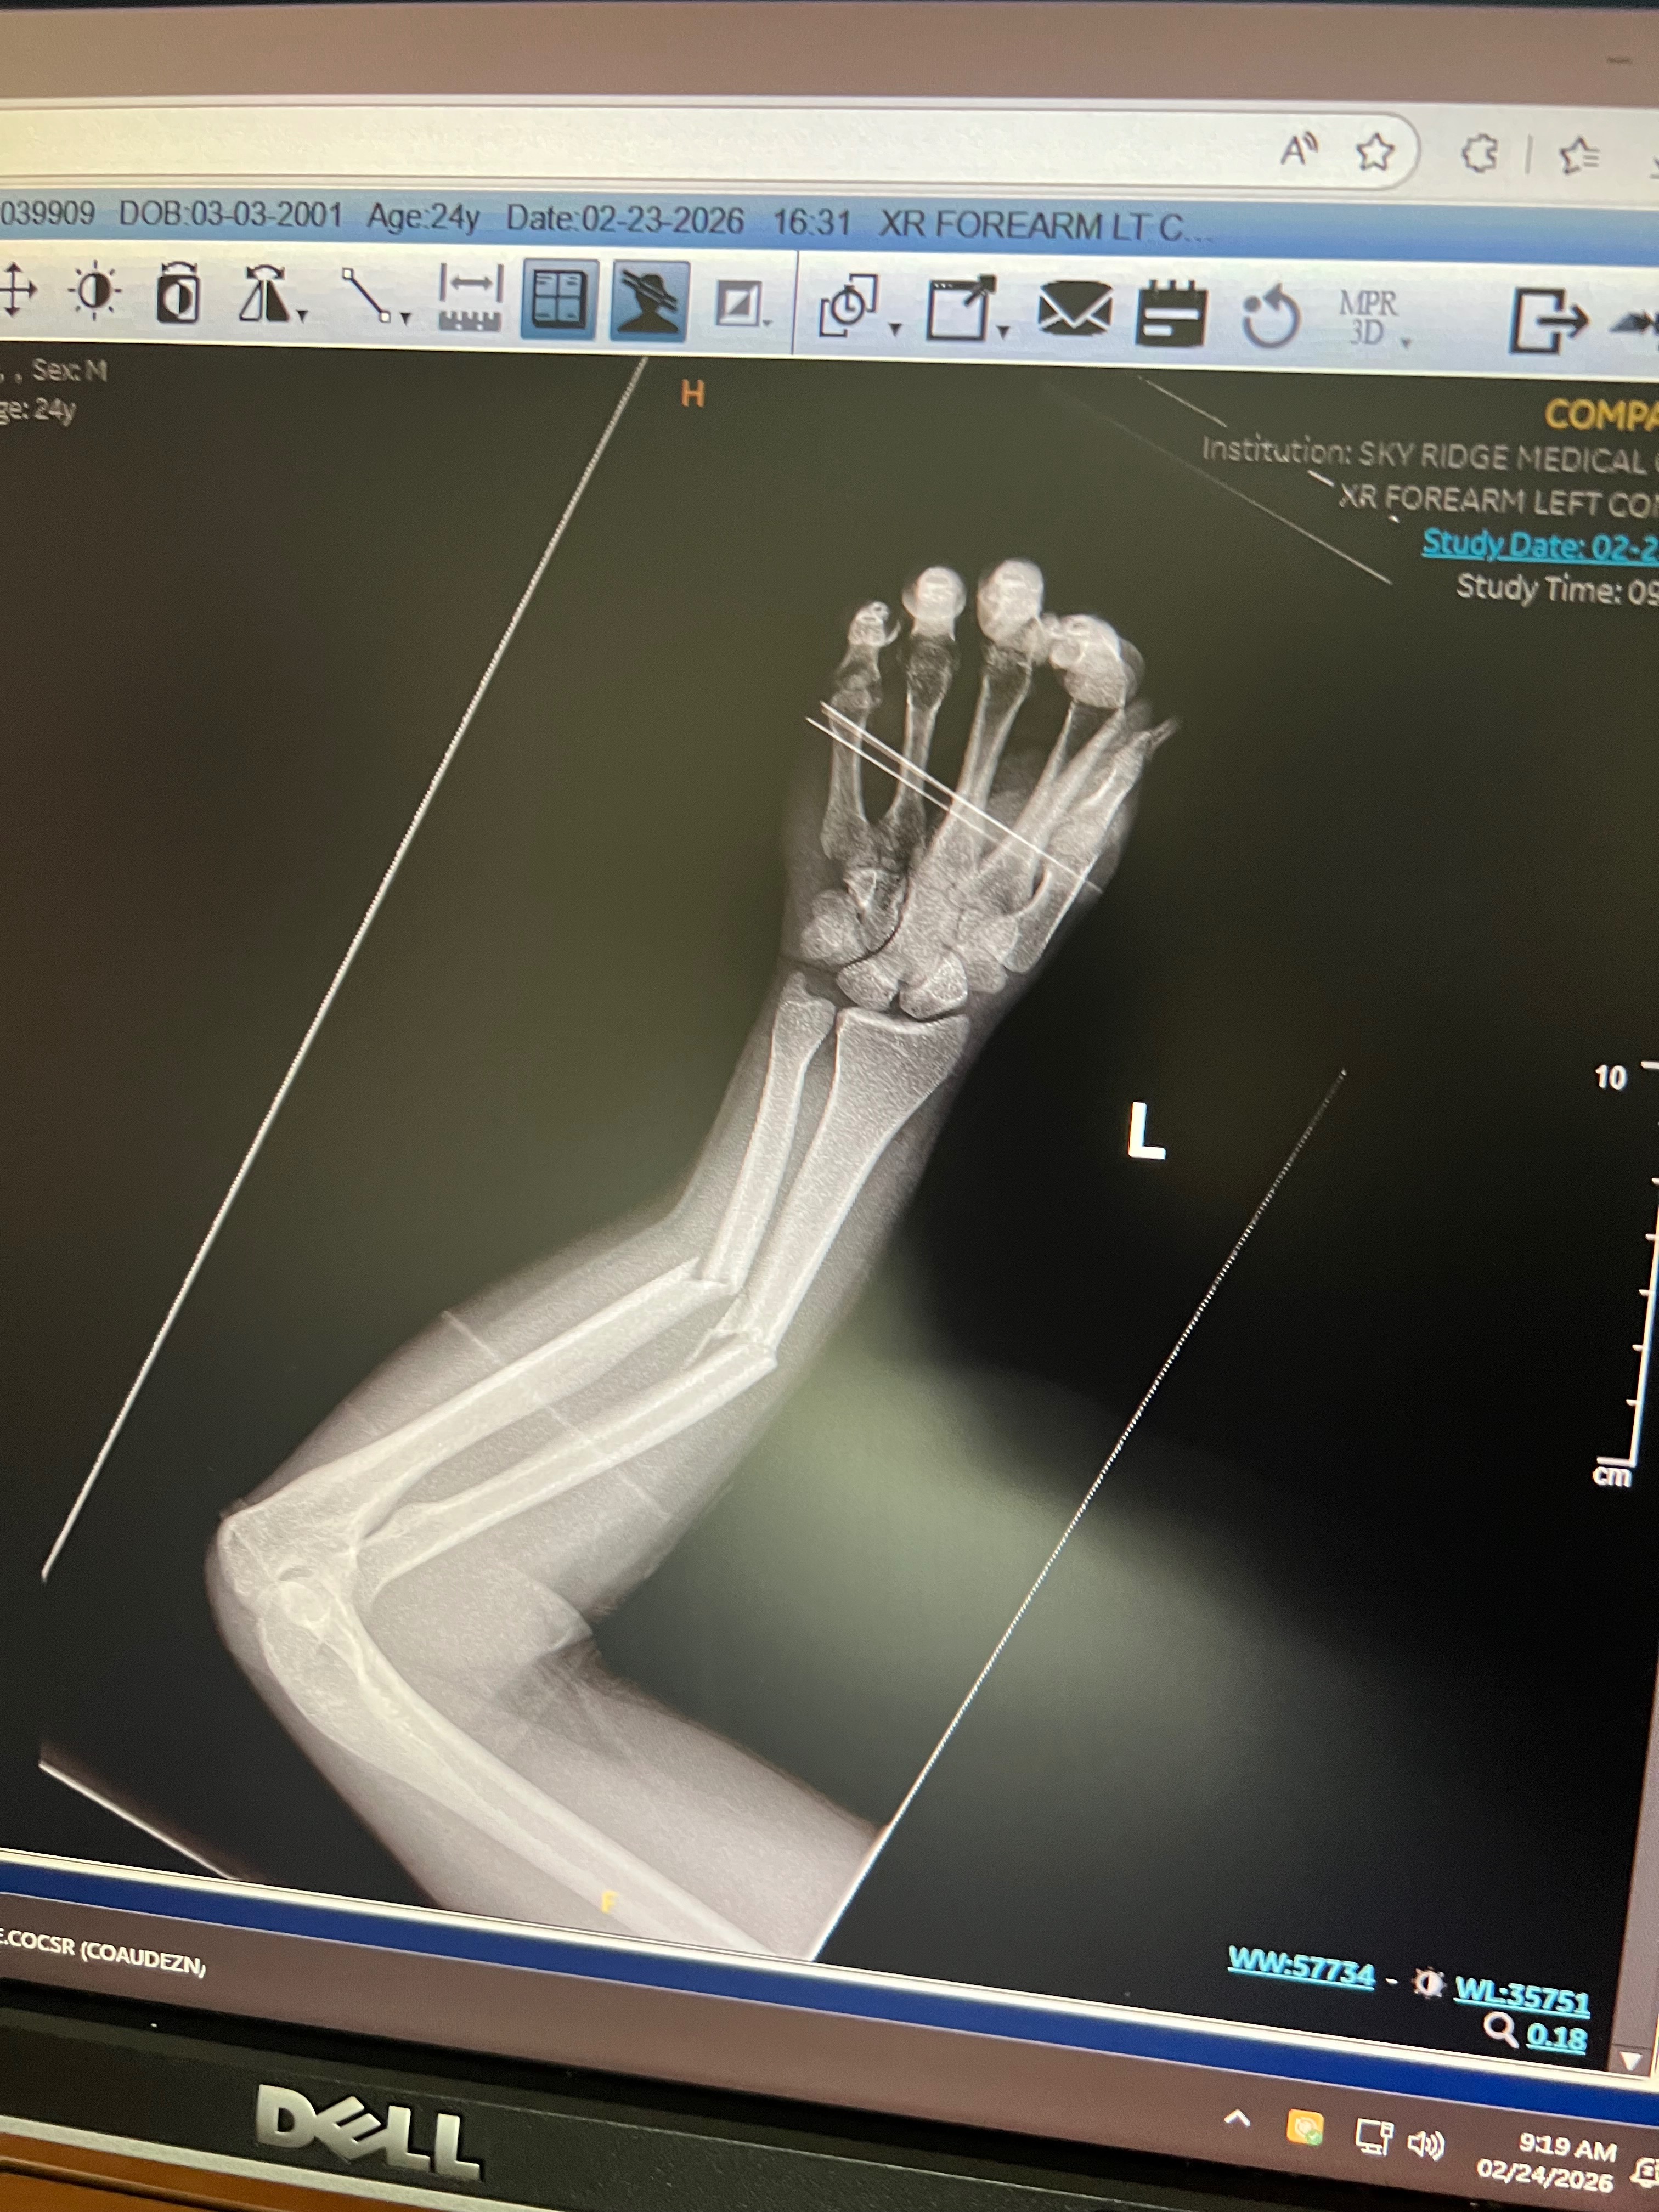

By the grace of God, Keshawn survived. He was immediately treated by first responders and taken to Skyridge Medical Center, where he stayed for 3 days, experienced emergency surgery, and a great deal of pain. Overall, he walked away with a mended but broken left arm and many other smaller and less serious wounds.

This young family is now facing unexpected medical expenses, ongoing treatment costs, and the challenge of recovering physically and financially. Keshawn is the primary provider for his family, and his focus right now is healing, physically and emotionally, so he can regain full use of his arm in 8-12 weeks and return to work to support Emma and their sweet little girl, Vienna.